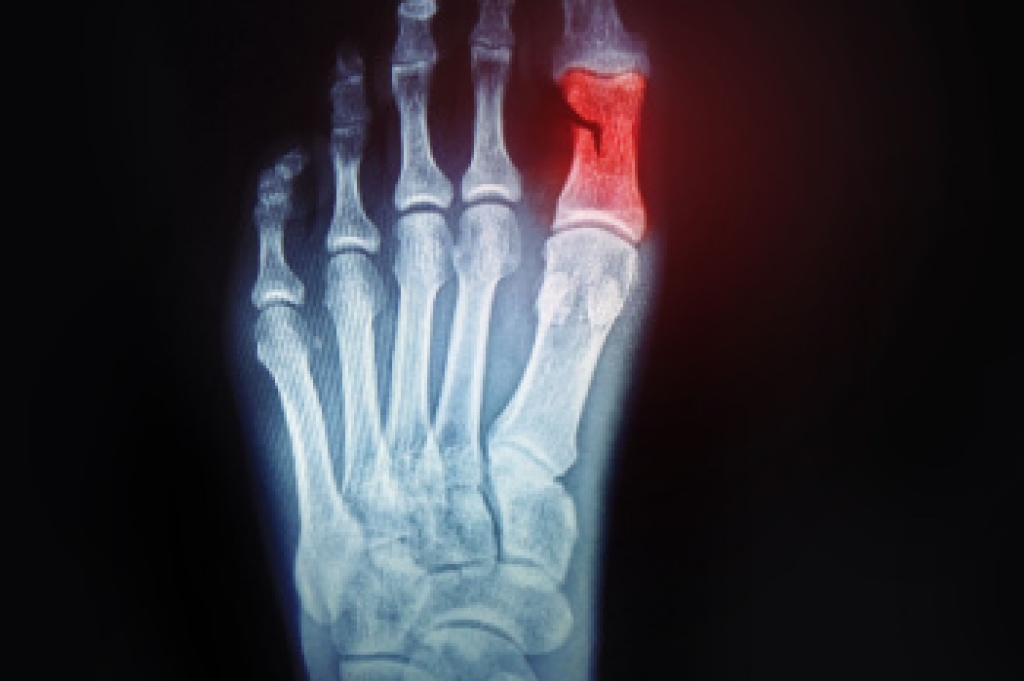

Broken toes, while often underestimated, can significantly impact daily activities and mobility. Common causes of broken toes include traumatic injuries such as stubbing or dropping heavy objects on the foot, as well as sports-related incidents and accidents. Symptoms of a broken toe typically include pain, swelling, bruising, and difficulty bearing weight on the affected foot. In severe cases, the toe may appear visibly misaligned or deformed, and there may be an audible popping or cracking sound at the time of injury. Additionally, individuals may experience numbness or tingling sensations in the affected toe. The appearance of a broken toe can vary depending on the severity of the injury, with some cases showing obvious signs of displacement or angulation, while others may have subtle swelling and discoloration. If you have fractured your toe, it is suggested that you consult a podiatrist who can perform an accurate diagnosis, and offer the treatment method that is best for you.

- Toe appears crooked or disfigured